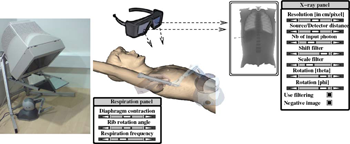

F. P. Vidal, and P. F. Villard.

We present a framework that combines evolutionary optimisation, soft tissue modelling and ray tracing on GPU to simultaneously compute the respiratory motion and X-ray imaging in real-time. Our aim is to provide validated building blocks with high fidelity to closely match both the human physiology and the physics of X-rays. A CPU-based set of algorithms is presented to model organ behaviours during respiration. Soft tissue deformation is computed with an extension of the Chain Mail method. Rigid elements move according to kinematic laws. A GPU-based surface rendering method is proposed to compute the X-ray image using the Beer–Lambert law. It is provided as an open-source library. A quantitative validation study is provided to objectively assess the accuracy of both components: (i) the respiration against anatomical data, and (ii) the X-ray against the Beer–Lambert law and the results of Monte Carlo simulations. Our implementation can be used in various applications, such as interactive medical virtual environment to train percutaneous transhepatic cholangiography in interventional radiology, 2D/3D registration, computation of digitally reconstructed radiograph, simulation of 4D sinograms to test tomography reconstruction tools. Keywords: X-ray simulation, Deterministic simulation (ray-tracing), Digitally reconstructed radiograph, Respiration simulation, Medical virtual environment, Imaging guidance, Interventional radiology training |

P.-F. Villard, F. P. Vidal, C. Hunt, F. Bello, N. W. John, S. Johnson, and

Purpose: We present here a simulator for interventional radiology focusing on percutaneous transhepatic cholangiography (PTC). This procedure consists of inserting a needle into the biliary tree using fluoroscopy for guidance. Methods: The requirements of the simulator have been driven by a task analysis. The three main components have been identified: the respiration, the real-time X-ray display (fluoroscopy) and the haptic rendering (sense of touch). The framework for modelling the respiratory motion is based on kinematics laws and on the Chainmail algorithm. The fluoroscopic simulation is performed on the graphic card and makes use of the Beer-Lambert law to compute the X-ray attenuation. Finally, the haptic rendering is integrated to the virtual environment and takes into account the soft-tissue reaction force feedback and maintenance of the initial direction of the needle during the insertion. Results: Five training scenarios have been created using patient-specific data. Each of these provides the user with variable breathing behaviour, fluoroscopic display tuneable to any device parameters and needle force feedback. Conclusions A detailed task analysis has been used to design and build the PTC simulator described in this paper. The simulator includes real-time respiratory motion with two independent parameters (rib kinematics and diaphragm action), on-line fluoroscopy implemented on the Graphics Processing Unit and haptic feedback to feel the soft-tissue behaviour of the organs during the needle insertion. Keywords: Interventional radiology; Virtual environments; Respiration simulation; X-ray simulation; Needle puncture; Haptics; Task analysis |